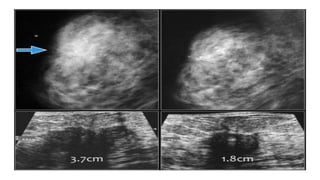

• #66 Here images of a biopsy proven malignancy. Due to the dense fibroglandular tissue the tumor is not well seen. Ultrasound demonstrated a 37 mm mass with indistinct and angular margins and shadowing. After chemotherapy the tumor is not visible on the mammogram. Ultrasound showed shrinkage of the tumor to a 18 mm mass, which was categorized as BI-RADS 6.